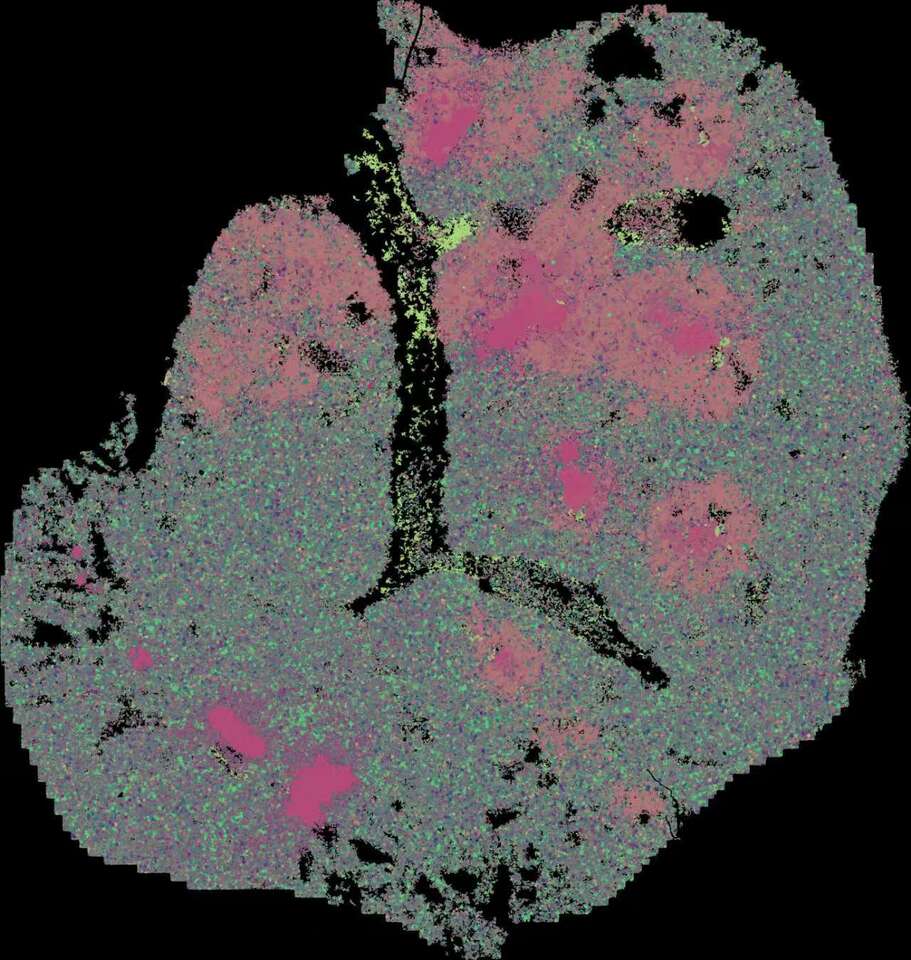

In our two companion studies recently published in Cell Discovery, we used SARS-CoV-2-infected Syrian hamsters as a model to investigate the whole process of pulmonary immune homeostasis from physiological condition, viral infection, viral clearance, to inflammation resolution. We applied an immunocartography technique that integrates spatial and single-cell transcriptomic sequencing via single-cell deconvolution and co-localization analysis. By charting the spatiotemporal distribution of immune cells across hamster lungs at single-cell resolution, we discover spatially co-localized dendritic cell (DC)-T cell immunity hubs in the alveolar regions, which play pivotal roles in responding and clearing SARS-CoV-2 infection. These DC-T immunity hubs are mainly composed of spatially co-localized Ccr7+Ido1+ dendritic cells, Cd160+Cd8+ T cells, and Tnfrsf4+Cd4+ T cells, which reside in the alveoli under physiological conditions at a low level (lower than 1%). Both the number and the size of DC-T immunity hubs rapidly increase at least as early as 2 days after SARS-CoV-2 infection.

We find that multiple myeloid cell types, including macrophages, DCs and neutrophils, are enriched in DC-T immunity hubs at 5 to 7 days after SARS-CoV-2 infection, especially a subpopulation of Slamf9+ macrophages. Therefore, we further analyzed the specific characteristics and the potential function of these Slamf9+ macrophages. We found that Slamf9+ macrophages may engulf SARS-CoV-2 and are resistant to cell deaths caused by SARS-CoV-2 infection because of the extremely high rates of SARS-CoV-2 RNA positivity and the significant expansion after SARS-CoV-2 infection, different from those tissue-resident alveolar macrophages. Besides, these macrophages might also secrete chemokines to recruit neutrophils, which is also involved in the function of DC-T immunity hubs, to clear SARS-CoV-2 together, and secrete IL-10 to induce an immunosuppressive niche that is co-localized by Isg12+Cst7+ neutrophils to prevent infection-induced injury. After viral clearance, Slamf9+ macrophages differentiate into Trem2+ and Fbp1+ macrophages and promote inflammation resolution, alveolar macrophage replenishment and tissue repair. Meanwhile, the DC-T immunity hubs decrease and restore to the physiological levels at about two weeks after infection.

Collectively, our study suggests that DC-T immunity hubs, together with Slamf9+ macrophages, function at the core of pulmonary immune surveillance by participating viral containment, viral clearance, and inflammation resolution. Experimental validations in hamsters, mice (and hACE2 transgenic mice), and human samples prove the wide presence of such DC-T immunity hubs in alveoli and their protective roles against infection and even cancer.

Schematic diagram

DC-T immunity hubs were physiologically detected in hamster lungs, which were mainly composed of spatially co-localized Cd160+Cd8+ T cells, Tnfrsf4+Cd4+ T cells and Ccr7+Ido1+ DCs. After SARS-CoV-2 infection, the immunity hubs expanded by recruiting Slamf9+ macrophages and Isg12+Cst7+ neutrophils to jointly clear viral infection. After viral clearance, the immunity hubs restored to physiological levels, and Slamf9+ macrophages may differentiate into Fbp1+ and Trem2+ macrophages, promoting inflammation resolution.